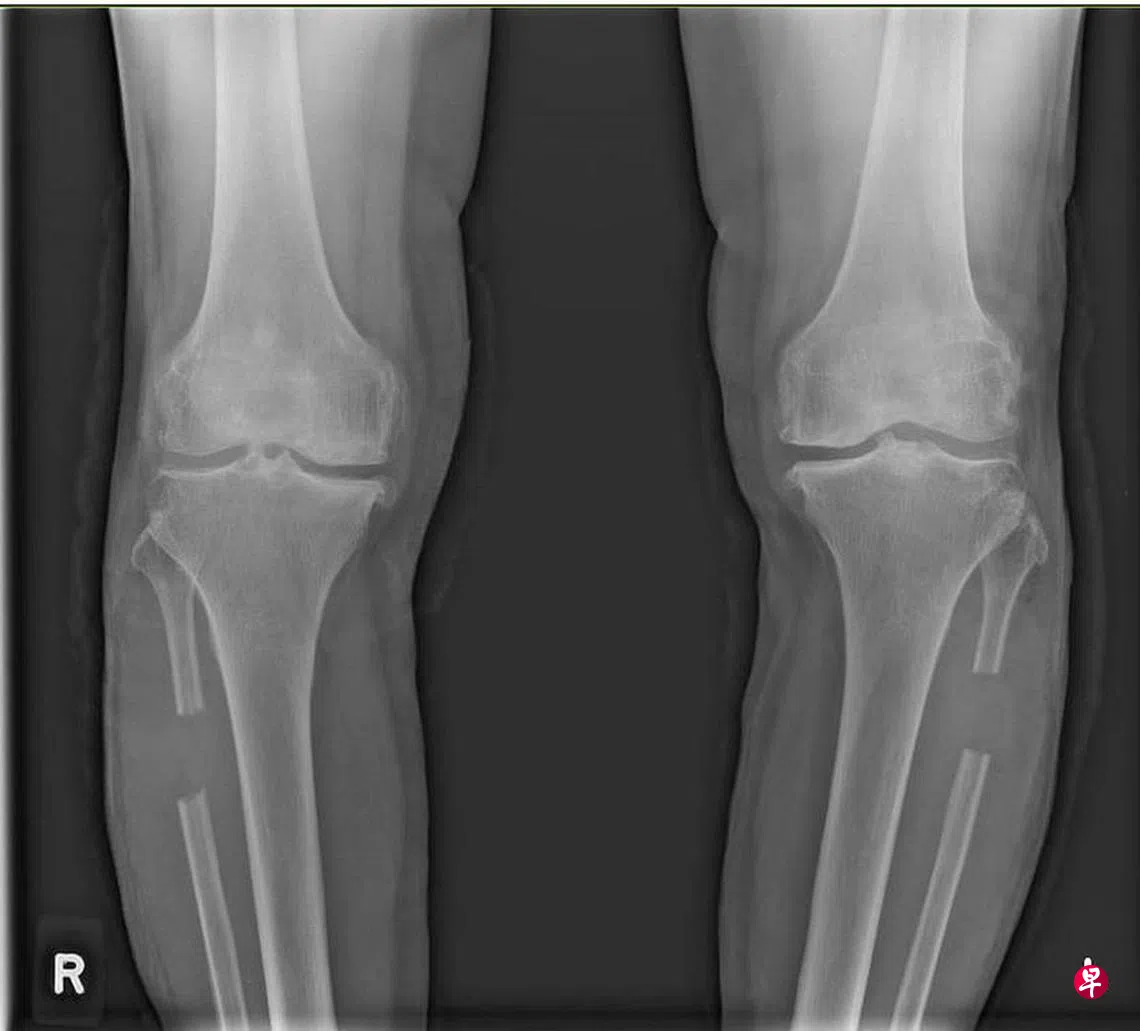

把支撑膝关节外侧的小腿腓骨截除约两公分,膝盖关节所承受的压力就能均匀分布于膝关节的内外侧,从而减少内外侧承受过多重量,造成长期磨损而导致疼痛。腓骨无须再次接上,周围的小腿肌肉也能固定住已截断的腓骨。